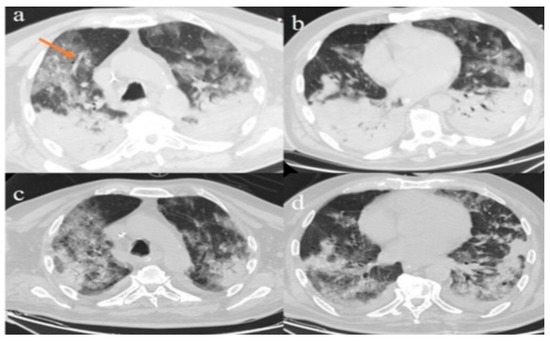

2.1. Case 1

2.2. Case 2